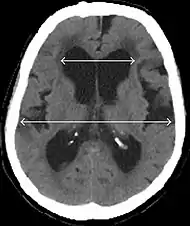

- Imaging from magnetic resonance imaging (MRI) or computed tomography (CT) is needed to demonstrate enlarged ventricles and no macroscopic obstruction to cerebrospinal fluid flow. Imaging should show an enlargement to at least one of the temporal horns of lateral ventricles, and impingement against the falx cerebri resulting in a callosal angle ≤ 90° on the coronal view, showing evidence of altered brain water content, or normal active flow (which is referred to as "flow void") at the cerebral aqueduct and fourth ventricle.

MRI scans are the preferred imaging. The distinction between normal and enlarged ventricular size by cerebral atrophy is difficult to ascertain. Up to 80% of cases are unrecognized and untreated due to difficulty of diagnosis.[9] Imaging should also reveal the absence of any cerebral mass lesions or any signs of obstructions. Although all patients with NPH have enlarged ventricles, not all elderly patients with enlarged ventricles have primary NPH. Cerebral atrophy can cause enlarged ventricles, as well, and is referred to as hydrocephalus ex vacuo.